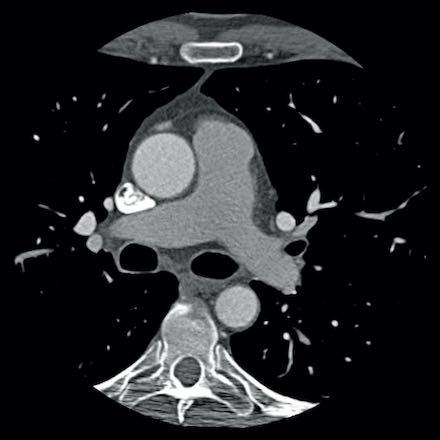

case 3 – Calcium score 0 and severe stenoses.

First, scroll through the CTA images.

How would you describe the findings on the coronary CTA?

The findings are:

- The total calcium

score of 0 indicates the absence of calcified plaque in the coronary

tree. - Severe stenosis

(70-99%) in the mid LAD and D2 branch.